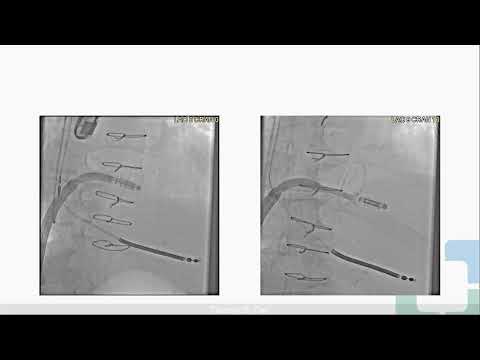

Percutaneous Techniques for Mitral Valve Repair and Replacement (COLIN M. BARKER, MD)

Ss 5 Structural Intervention - Mitral Valve Freemedbooks.com

Ss9 TEER for Mitral Regurgitation Secondary to Mitral Ring Dehiscence Freemedbooks.com